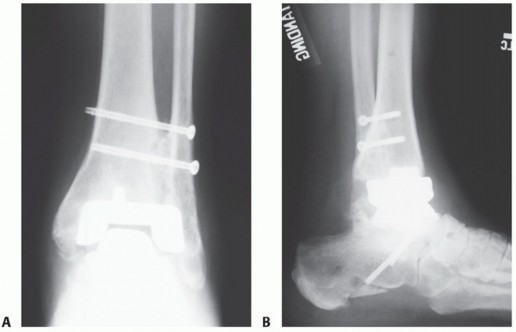

- TECH FIG 6 • A,B. Preoperative AP and lateral views of failing Agility total ankle prosthesis. C,D. Postoperative AP and lateral views after placement of femoral head allograft (soaked in concentrated bone marrow aspirate) demonstrate the excellent stability of an intramedullary device in a complicated revision situation.

- TECH FIG 6 • A,B. Preoperative AP and lateral views of failing Agility total ankle prosthesis. C,D. Postoperative AP and lateral views after placement of femoral head allograft (soaked in concentrated bone marrow aspirate) demonstrate the excellent stability of an intramedullary device in a complicated revision situation.